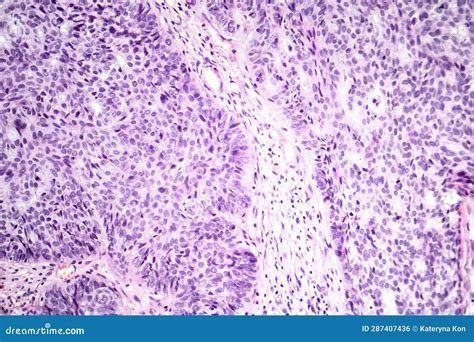

To navigate the nuances of skin health, we must first clarify the terminology. Basal cell carcinoma (BCC) is the most common form of skin cancer, originating in the basal cells of the epidermis. In contrast, melanoma is a much rarer but significantly more aggressive form of cancer that originates in the melanocytes—the cells responsible for producing pigment. While a physician would not diagnose a patient with "Basal Cell Melanoma," the confusion often stems from the fact that both conditions are diagnosed after similar dermatological screenings. Early detection remains the gold standard for survival, regardless of the classification.

One of the most effective ways to manage your health is by performing monthly skin self-exams. When monitoring for potential signs of skin cancer, dermatologists often refer to the ABCDE rule, primarily for melanoma, while looking for "pearly" or translucent bumps for basal cell carcinomas. Knowing what to look for can be the difference between a minor procedure and a major surgical intervention.